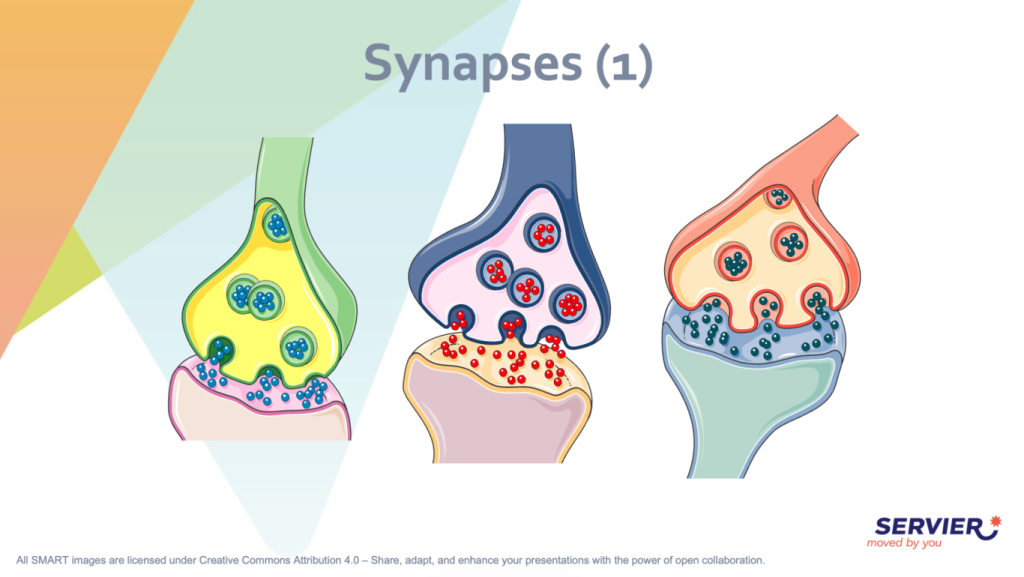

1. SMART - Servier Medical ART

◦ Propósito: Es una biblioteca con más de 3,000 ilustraciones médicas gratuitas diseñadas para ayudar a estudiantes, investigadores y profesionales de la salud a explicar conceptos complejos.

◦ Contenido: Incluye imágenes sobre anatomía (sistema cardiovascular, digestivo, nervioso, etc.), biología celular, especialidades médicas y elementos generales como equipos de laboratorio o animales.

◦ Licencia: Las imágenes están bajo la licencia Creative Commons Attribution 4.0 (CC BY 4.0), lo que permite compartirlas, adaptarlas e incluso usarlas para fines comerciales, siempre que se otorgue el crédito correspondiente al creador.

◦ Recursos adicionales: Ofrece herramientas educativas, videos tutoriales y "kits" de imágenes por categorías para facilitar la creación de presentaciones y artículos científicos.